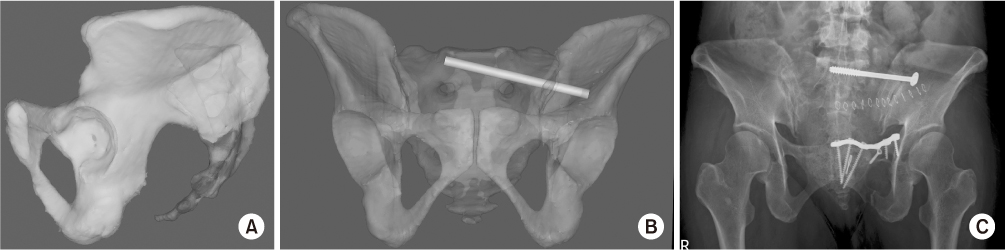

Fig. 5

(A) Unstable pelvic ring injury in a 20-year-old male showing the involvement of spinal canal and comminution of upper sacral surface. (B) The trans-sacral trans-iliac screw was performed after the anterior fixation for achieving the functional reduction of sacrum. (C) The radiographs after 12 months showed neither a loss of reduction nor screw back-out.